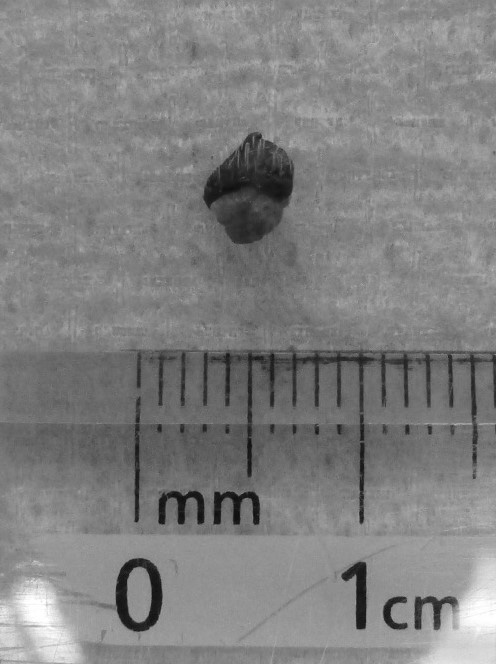

加齢に伴って、まぶたにシコリができることがあります。眼球に対して刺激になって結膜炎や痛みの症状が出る、視覚の妨げになるなどの場合には手術をおすすめします。再発のないようにイボを根っこから、ノッチができないよう「楔形」や「四辺」をイメージに切り取って縫い合わせます。アイラインが確実にピッタリ合うように丁寧に縫うことが仕上がりの良し悪しを決めます。今回の子は病理組織検査の結果「マイボーム腺腫」でした。